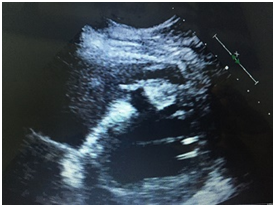

Patient was thrombolysed properly, intubated and sedated and taken to cath lab for urgent PTCA. Echocardiography also showed severe LV systolic dysfunction, a kinetic mid and apical portions, large ventricular septal defect VSD sized 1.3 cm in the form of an oblique tunnel with significant left to right shunt (Figure 1).

Figure 1 Post MI VSD by echocardiography.